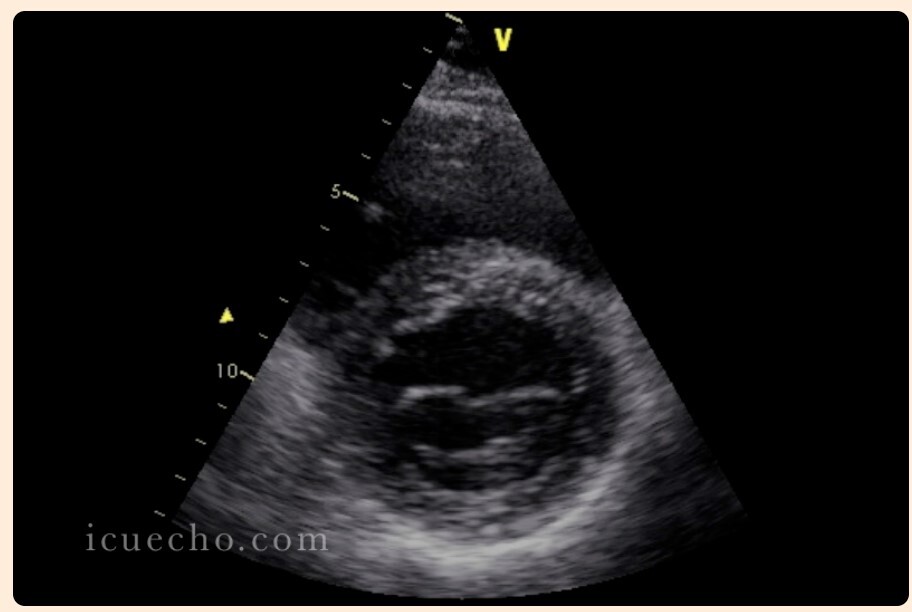

Parasternal short axis view - start with PLAX, rotate probe 90 degrees until probe indicator is pointed at the left shoulder, and fan down and medially. Left and right ventricles, can see anterolateral and posteromedial papillary muscles.